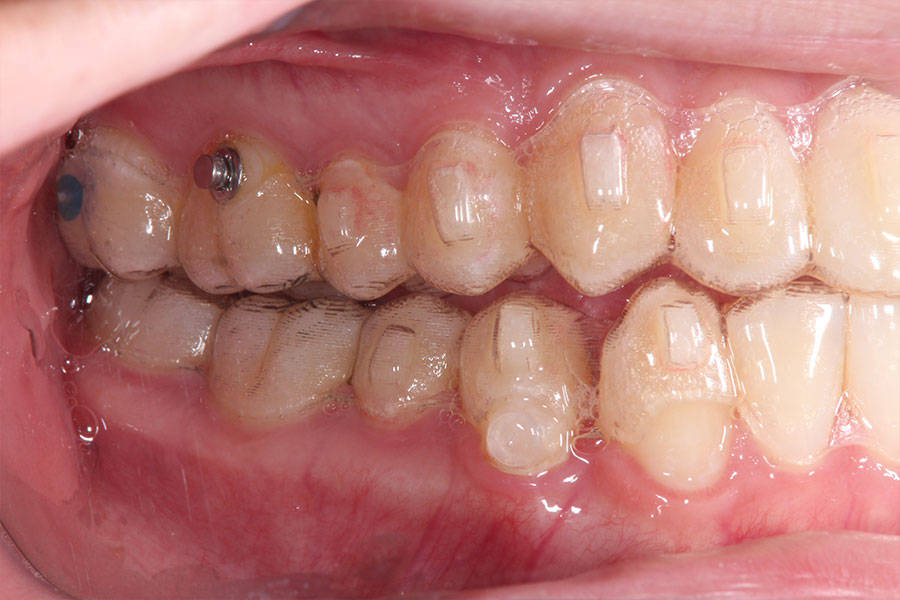

Before -側面-

After -側面-

| 施術内容 | ワイヤー矯正から、目立ちにくくメタルフリーなインビザラインへ変更しました。 金属アレルギーの不安が軽くなり、取り外しできることで清掃性も向上。見た目も自然で、治療中のストレスが少ない矯正方法です。 |

|---|---|

| 治療期間 | 2年間 |

| 費用 | インビザラインフル 767,800円 リテーナー 30,000円 |

| リスク・副作用 | 治療にともない、歯の破折や歯質の削合、場合によっては抜歯が必要となることがあります。また、金属や補綴物を除去する際に、完全に除去できない場合もあります。 |